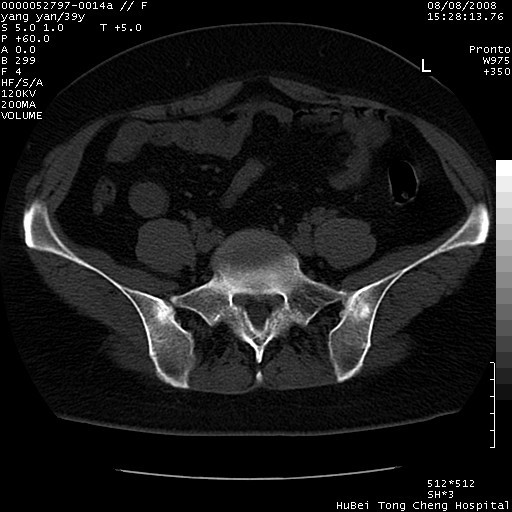

患者 女,39岁。因外伤检查,偶然发现。

典型!双侧骶髂关节致密性骨炎。

典型!病变主要累及双侧髂骨。常见于育龄期妇女。

致密性骨炎,一般不跨越关节面,可是这个骶骨关节面也有硬化。

髂骨致密性骨炎系一种以骨质硬化为特点的非特异性炎症,有高度致密的骨硬化现象,尤其以髂骨下2/3更为明显,但关节间隙则无改变。因位于骶髂关节,且该关节症状明显,故又称之为“骶髂关节致密性骨炎”。 本病90%以上为中年女性,以妊娠后期、尤其分娩后为多见,亦可见于尿路或女性附件慢性感染后,或盆腔内其他感染。此外,臀骶部的外伤亦可诱发或引起本病。  妊娠、分娩及外伤均可引起骶髂关节韧带的撕裂而易使局部的血供受阻。因此早期局部呈现充血、水肿及渗出增加等,渐而局部出现增生与变性反应,随着胶原纤维的致密化而向硬化演变;血管形成厚壁血管,易闭塞而引起髂骨耳状面处缺血和缺氧,骨质呈现硬化性改变,以致手术时局部出血较少。骶髂关节囊壁显示纤维增生、弹性降低及松动样改变。继发于盆腔内炎症者亦出现相类似的病理改变,可能系细菌内毒素作用所致。